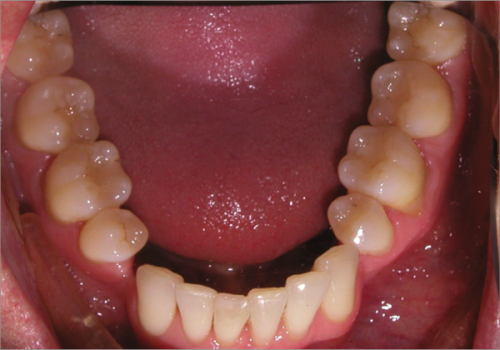

44 year old female:

Diagnosis:

- Upper and lower arch collapse due to missing teeth

- Retrusive angulation of upper & lower front teeth

- Severe collision and wear of front teeth

Treatment:

- Combination of Invisalign and braces

- Creating space for placement of an implant in the lower arch

- 28 months